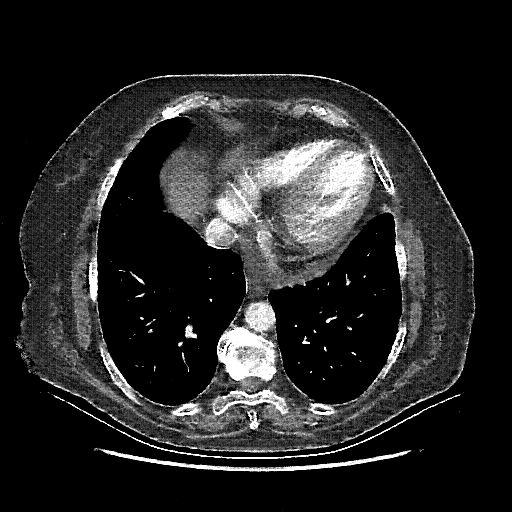

Targeted Slice 70 - Mediastinum Window Analysis (Generated vs Real Venous)

0.716

Mediastinum SSIM

38.6

Mediastinum RMSE

16.1

Mediastinum MAE

Average Mediastinum Window Metrics Across All Slices (101 slices) - Generated vs Real Venous

0.683

Mediastinum SSIM (Avg)

41.1

Mediastinum RMSE (Avg)

18.4

Mediastinum MAE (Avg)

Generated VENOUS CT scan (A→B translation)

Full window (WL 1023.5, WW 4095 β†’ Low βˆ’1024, High +3071)

Mediastinum window (WL 40, WW 400 β†’ Low βˆ’160, High +240)